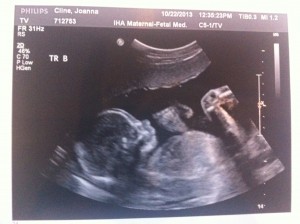

Hello! I had my bi-weekly ultrasound today and, if a triplet pregnancy appointment could be uneventful, this one was it!

Everything still looks great. The triplets are growing but we won’t have another growth scan until my 22wk appointment. Heart beats look good and it’s clear they’re getting bigger (Today’s pictures attached.)

I’m feeling movement but mostly from triplet B. My dr said to just give it a few weeks and it will feel like a conga line in my belly.